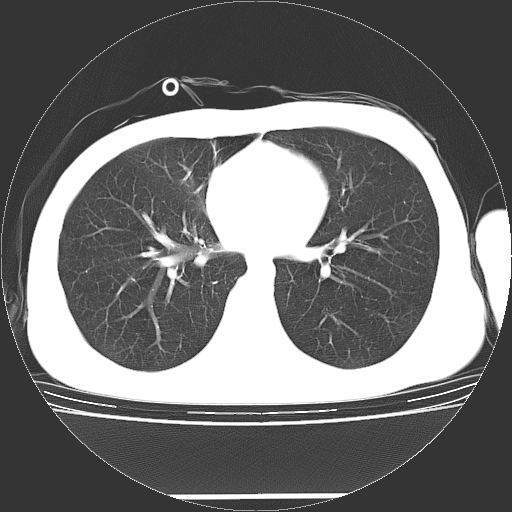

标题: CT19767:男,20岁,右侧气胸行闭式引流术后五天CT检查。 [打印本页]

标题: CT19767:男,20岁,右侧气胸行闭式引流术后五天CT检查。

男,20岁,右侧气胸行闭式引流术后五天ct检查看肺内是否有肺大泡,纵隔窗未见异常,未上传。

未见肺大泡影

右肺未见确切肺大泡。

1)右侧胸腔闭式引流术后导管留置。2)右肺未见肺大泡。

未见肺大泡,还有微量气体。